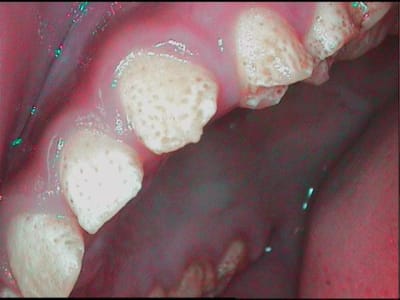

jeune patiente 11ans, je l'ai suivie il y a quelques années, pour les lacteales et sans probleme.

je la revois aujourd'hui, 11ans, et la denture definitive ne dit rien de bon pour son avenir....

je connais la famille, il n'y a aucun antécédent (connu), le controle de plaque est tres bon (elle a gardé en memoire les conseil d'hygiène, tant mieux et heureusement!!!), sa santé generale est tres bonne, ses habitudes alimentaires ne me laisse rien craindre...

pour les anterieures j'aimerais eviter les facettes, et m'orienter vers des prepa pelliculaires, pour les post je peux sceller les puits et fissures aux verres ionomeres, mais pour le "piqueté" général d'email, en buccal interprox, etc...